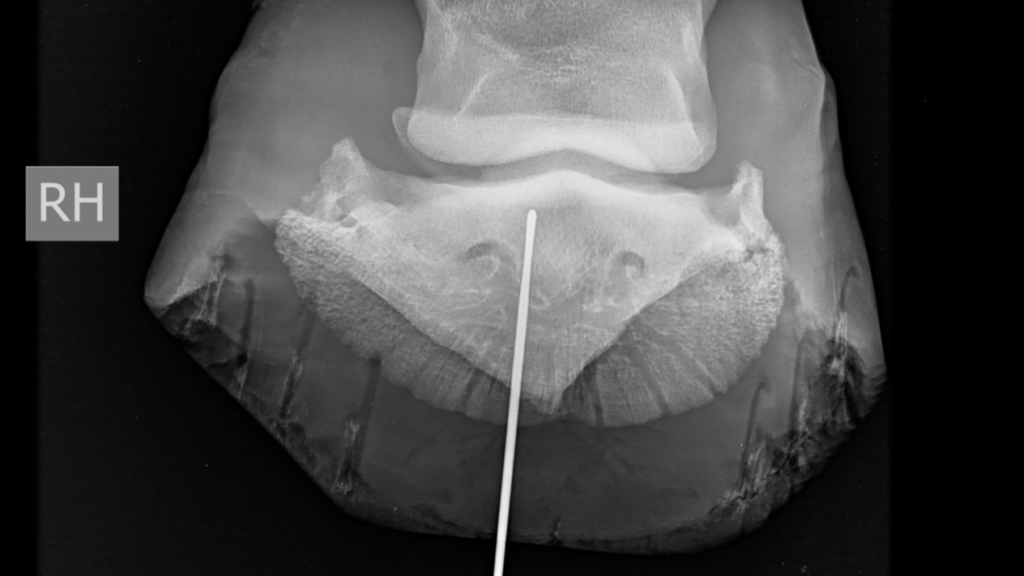

Warmbloedpaard met nageltred

Anamnese 12-jarig warmbloedpaard. Het paard werd op de weide aangetroffen met een nagel ter hoogte van de rechterachtervoet, penetrerend in de zool ter hoogte van...